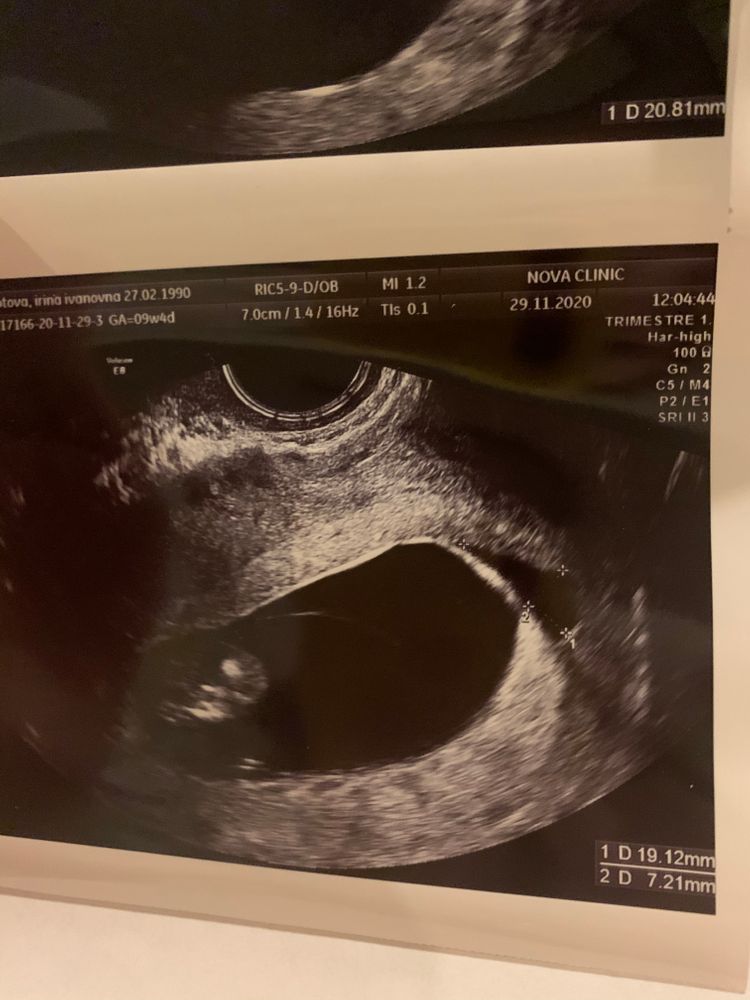

Сегодня в 9+4 недели была на узи в Нова Клиник и встала там на учёт, так вот тут мне написали что матка кзади и хорион преимущественно по передней стенке. 🤨 Аппарат у них экспертный. Мне всю жизнь говорили что у меня матка кзади. Нова Клиник больше доверяю, чем мать и дитя, там мне вообще не понравилось. Но блин, как может быть по разному?

Еще сегодня нашли небольшую гематому 20х7 мм. Прописали утрожестан 200 3 раза в день. Переживательно. Расположена она в дне матки.